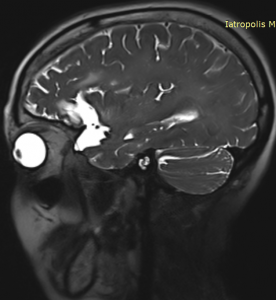

Η μαγνητική εγκεφάλου ανέδειξε ευμεγέθη αραχνοειδή κύστη δεξιά κροταφικά με σημαντική πίεση επί του υγιούς εγκεφάλου και παρεκτόπιση των δομών της μέσης γραμμής (έμμεση ένδειξη αυξημένης ενδοκράνιας πίεσης).

Η ασθενής παρουσίασε άμεση βελτίωση της όρασής της. Ο απεικονιστικός έλεγχος με μαγνητική τομογραφία 6 μήνες μετά την επέμβαση ανέδειξε σημαντική μείωση της κύστης και της πίεσης επί του υγιούς εγκεφάλου.

Στη συγκεκριμένη περίπτωση όμως η κύστη ήταν εξαιρετικά μεγάλη και πίεζε σημαντικά τον παρακείμενο εγκέφαλο. Αυτό φαίνεται ξεκάθαρα από τη λεγόμενη “παρεκτόπιση των δομών της μέσης γραμμής”. Αυτό σημαίνει ότι ο εγκέφαλος πιέζεται από τη μία μεριά τόσο πολύ, που οι φυσιολογικές εγκεφαλικές δομές παρεκτοπίζονται. Επιπλέον, η αυξημένη ενδοκράνιος πίεση προκάλεσε οίδημα στα οπτικά νεύρα, γι’ αυτό και η ασθενής είχε προβλήματα με την όρασή της.

Το αποτέλεσμα 6 μήνες μετά είναι εξαιρετικό, τόσο σ’ ότι αφορά στη μαγνητική τομογραφία όσο και σ’ ότι αφορά στα συμπτώματα της ασθενούς.